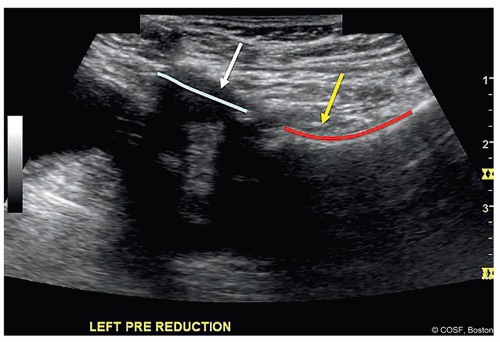

Hip reduction is assessed both prior to casting and in spica cast via an anterior/transinguinal approach (Figures 20.3,20.4,20.5)

This imaging has been validated against cross-sectional imaging1

Figure 20-5 ▪ In cast ultrasound from anterior view. Cast is modified to allow access to hip. (Courtesy of Children’s Orthopaedic Surgery Foundation.)